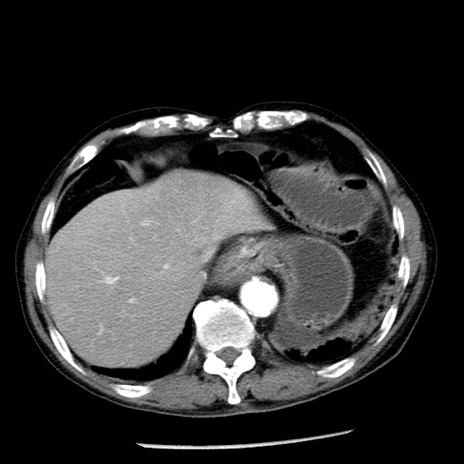

症例26(横断像)

【症例】80歳代男性

【主訴】嘔吐

【現病歴】昨晩2回嘔吐あり、今朝になっても嘔吐あり。来院。

【既往歴】胃潰瘍

【身体所見】意識清明、BT 37.6℃、BP 166/95mmHg、HR 100bpm、SpO2 97%、腹部:平坦・軟、腸蠕動音聴取良好、圧痛なし。

【データ】WBC 21900、CRP 1.46